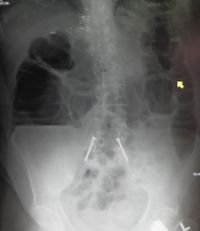

تتمثل أهم طرق التشخيص التي يمكن إجراؤها في حالة انسداد الأمعاء في اختبارات الدم أو عمل أشعة إكس على البطن أو الأشعة المقطعية و/أو أشعة الموجات فوق الصوتية. وإذا ما تم اكتشاف وجود ورم أو تكتل في الأمعاء، فقد يتم استئصال نسيج منه لتحليله وفحصه لمعرفة طبيعة هذا الورم أو التكتل.

من ضمن الأشياء التي يكشف عنها التصوير الإشعاعي وجود انتفاخ بالأمعاء ووجود مستويات متعددة (أكثر من ستة مستويات) من السوائل والغازات في صور الأشعة التي تؤخذ على البطن والمريض في وضع الاستلقاء على الظهر تارة والوقوف تارة أخرى.

وعلاوةً على ذلك، فمن الممكن استخدام حقنة الباريوم الشرجية أو صور أشعة ملونة للأمعاء الدقيقة أو الأشعة المقطعية لتحديد درجة انسداد الأمعاء، وما إذا كان الانسداد جزئيًا أم كليًا، وكذلك لمعرفة سبب الانسداد.